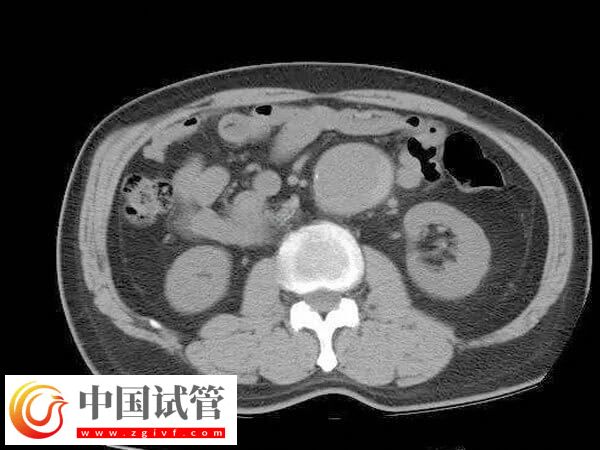

4、利用腹腔鏡探查盆腔以了解子宮大小形態(tài)和位置與周圍臟器關系。